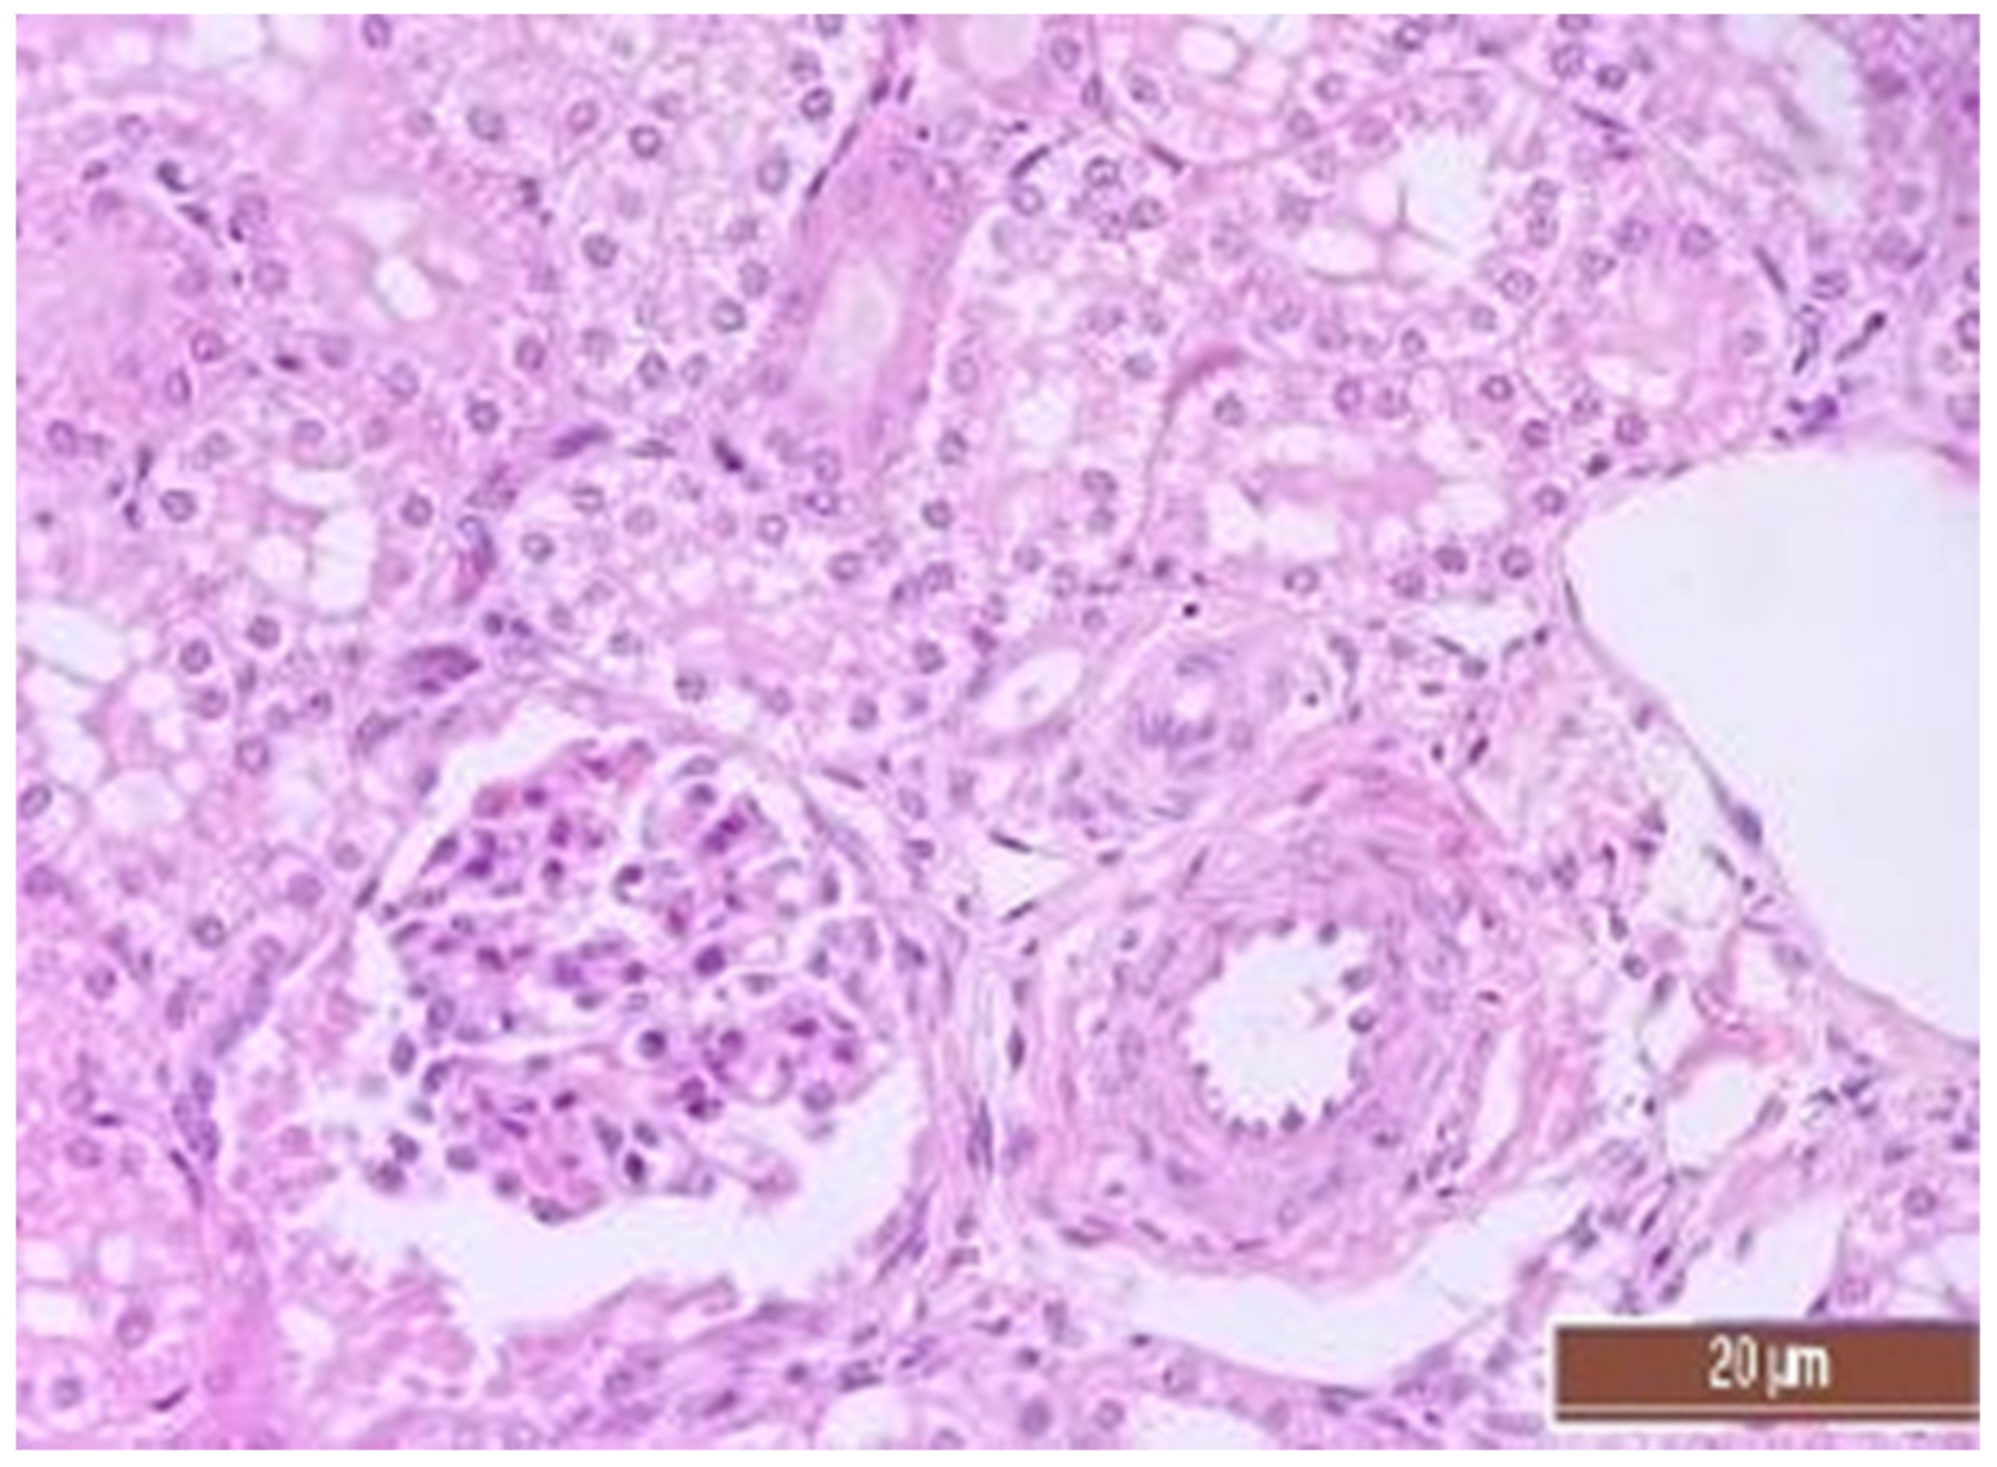

3.4. Pathology of Kidneys

| Value | Group | Value, Point | Mann–Whitney U-Test |

|---|---|---|---|

| Dystrophy of the epithelium of the tubules | CPB-contr, n = 25 | 2 (1; 3) | p = 0.49 |

| CPB-NO, n = 25 | 1 (1; 2) | ||

| Lymphoplasmocytic infiltration | CPB-contr, n = 25 | 0 (0; 1) | p = 0.37 |

| CPB-NO, n = 25 | 1 (1; 1) | ||

| Hyperemia | CPB-contr, n = 25 | 2 (2; 3) | p = 0.55 |

| CPB-NO, n = 25 | 3 (2; 3) |